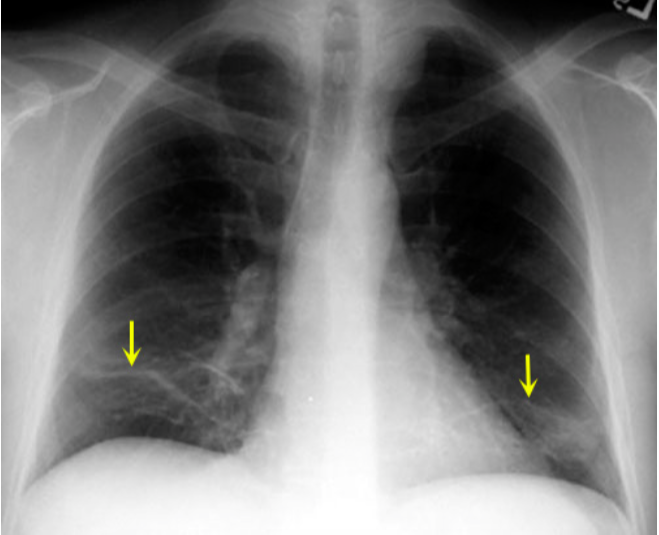

What type of atelectasis is this?

Plate Like (part of Adhesive)

What is plate like atelectasis?

It is due to the focal loss of surfactant

What is the cause of plate like atelectasis?

It is either due to loss of CO2 or oxygen. CO2 and oxygen maintain the integrity of surfactant.